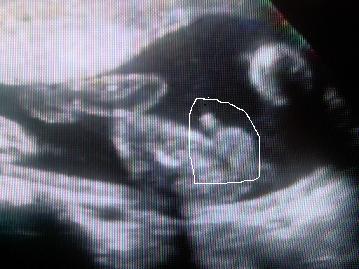

Úgy szerettem, amikor mocorogtak. Habár Gréti olyan kis finoman mozgott, hogy néha már azt mondtam, hogy megyek a védőnőkhöz, hallgassák meg a szívhangját, hogy él-e még ez a gyerek

De aztán mindig rúgott 1-2-t, hogy megnyugodjon az anyja